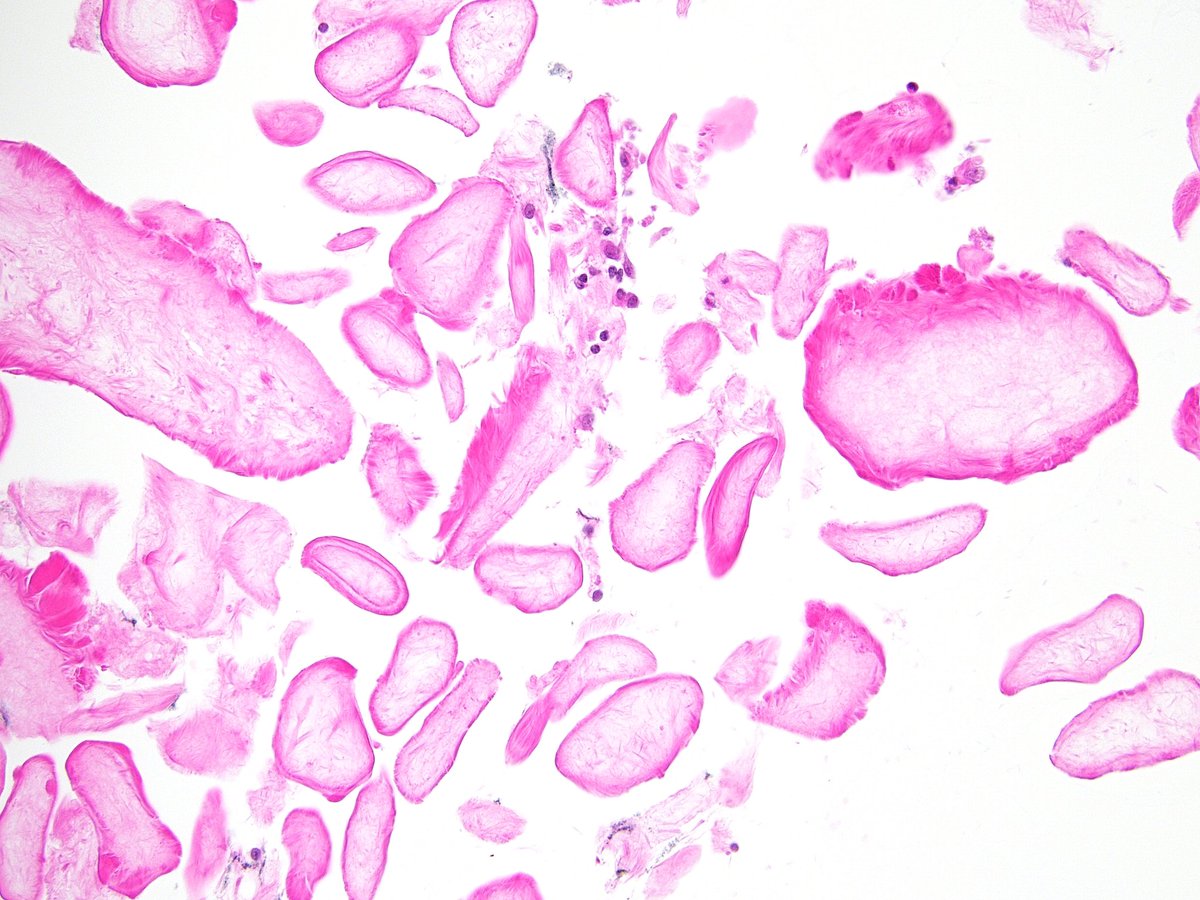

A 2.5-centimeter, clearly defined tumor of the lower lobe of the right lung in a 32-year-old woman, accidentally detected by fluorography. A smear from the tumor and the frozen section. The woman also has multiple AML of the left kidney. What do you think? #cyto #pathology